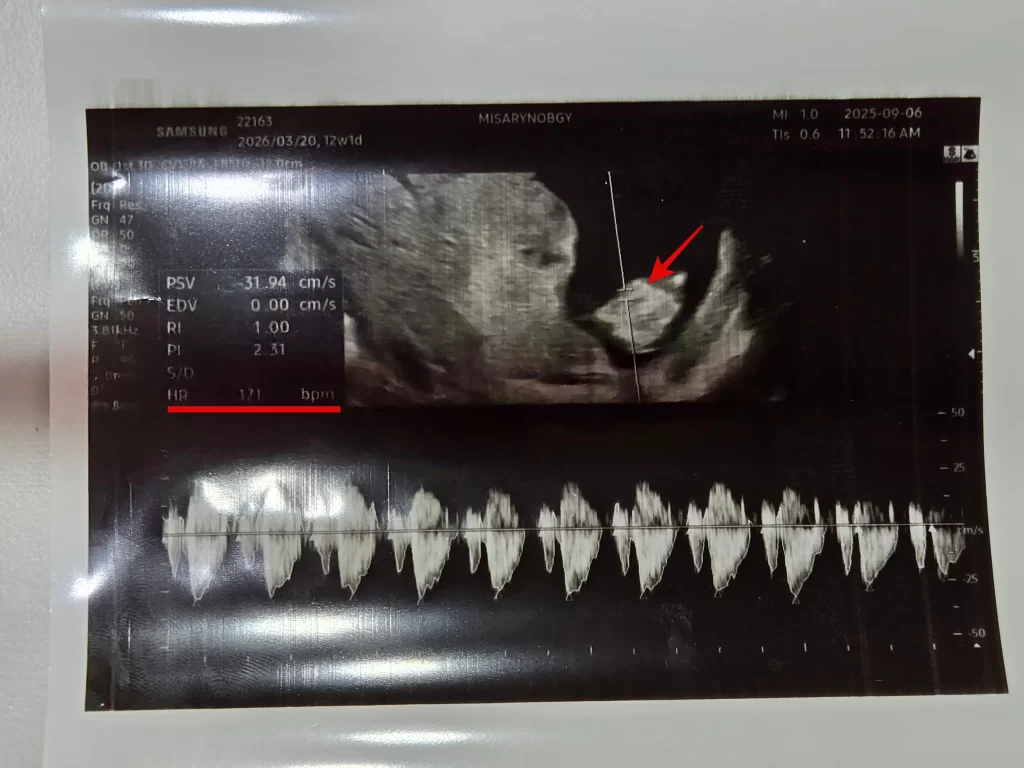

1차 기형아 검사는 전적으로 초음파 검사로 진행됐다. 실시간으로 아이의 상태를 보면서 이것 저것 확인해주셨다.

4.심장 박동

이번에도 아이의 심장 박동을 들을 수 있었다. 171bpm 으로 정상 범위였다. 이 시기가 태아 심장이 가장 활발히 뛰는 시기라고 한다.

팔다리도 볼 수 있었다.

지난번 초음파와는 확실히 달랐던 게 아이가 움직이는 걸 실시간으로 볼 수 있었다. 움직이기도 하고 심지어 옆으로 돌아서 눕는 것까지 보여서 신기했다.